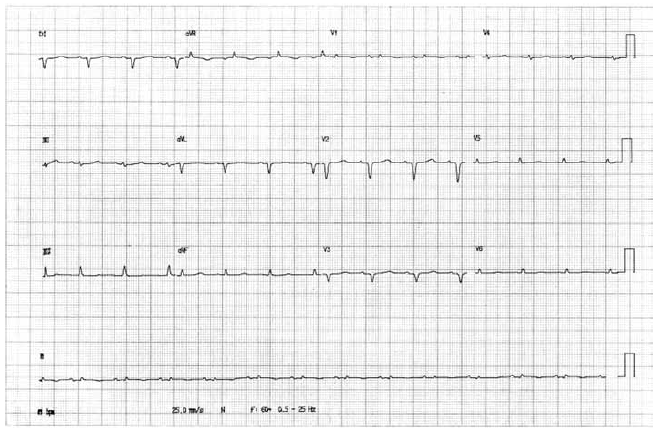

Paciente jovem, sexo masculino, comparece para avaliação cardiológica em decorrência de síncope sem pródromo ocorrida há cerca de 15 dias, durante compra no supermercado. O paciente não faz uso de medicamentos, seu exame físico é normal, e ele refere que o pai teve morte súbita aos 40 anos.

O eletrocardiograma desse paciente está ilustrado a seguir.

O tratamento definitivo deve ser feito com